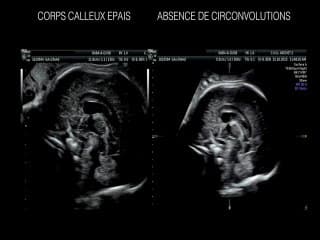

Le Pr Marc Zerah évoque les lésions médullaires.1ère partie:M. Zerah insiste sur la nécessité d'un diagnostic précis par l'imagerie (écho en 1ère ligne) IRM et la biologie, tout en soulignant la difficulté d'établir un pronostic pour ces enfantsLes tentatives de diagnostic précoce sont nécessaires: au 1er trimestre petit BIP, rapport BIP sur DAT.Deux images sont normales: le kyste du filum et le ventricule du filum.Tout repose sur le caractère ouvert ou fermé de la lésion.La myéloméningocèle (MMC) est une lésion ouverte non recouverte par la peau, associée à une déformation du crâne, et à malformation d'Arnold Chiari.Ses Conséquences sont le retard mental, l'hydrocéphalie, la malformation d'AC et les troubles moteurs et sphinctériensPour Marc Zerah, Il n'y a pas de MMC sans malformation d'Arnold Chiari. Cette dernière est rarement symptomatique à la naissance.Ce qui permet au chirurgien de donner un pronostic moteur, c'est le niveau osseux de la lésion.(Une diapo rappelle le niveau de terminaison du cône médullaire au cours de la gestation)En dessous de S1, l'enfant marcheraEntre L5 et S1 la marche est difficile et le pied est déformé.Au niveau de L4 la marche est difficile (quadriceps atteint, impossibilité de verrouiller le genou)Au dessus de L2 l'enfant ne marchera pasTous les autres dysraphismes fermés (recouverts par la peau) sont de bon pronostic à 70/80%. Il n'y a jamais d'urgence néonatale.Ces enfants auront une écho à la naissance, une IRM à 3 mois, certains ne seront jamais opérés, et 80/90% iront bien à l'âge adulte.2è partie:M.Zerah rappelle la chronologie des évènements qui ont amené à la chirurgie in utero de la MMC.L'étude MOMS (Managment of Myelomeningocele study) et l'essai PRIUM.Il donne les résultats de leur expérience, parle de la recherche en cours. En conclusion, il insiste sur la nécessité d'un diagnostic échographique précoce, la précision du niveau osseux de la lésion.Attention aux formes syndromiques et au diagnostic différentiel de la LDM.